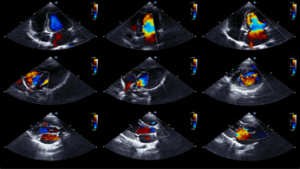

L’ecocolordoppler è un esame ( diagnostica per immagini) che viene utilizzato per analizzare malattie delle arterie, delle vene e quindi del cuore. Un’analisi dettagliata, finalizzata allo studio e al monitoraggio del flusso ematico nei vasi sanguigni grazie alla diagnostica per immagini.

L’ecocolordoppler è un esame ( diagnostica per immagini) che viene utilizzato per analizzare malattie delle arterie, delle vene e quindi del cuore. Un’analisi dettagliata, finalizzata allo studio e al monitoraggio del flusso ematico nei vasi sanguigni grazie alla diagnostica per immagini.

L’ecocolordoppler è una metodologia diagnostica che fa parte della “famiglia” degli ecodoppler, ovvero dei metodi che sfruttano il principio Doppler del rimbalzo di ultrasuoni all’interno dei vasi sanguigni.